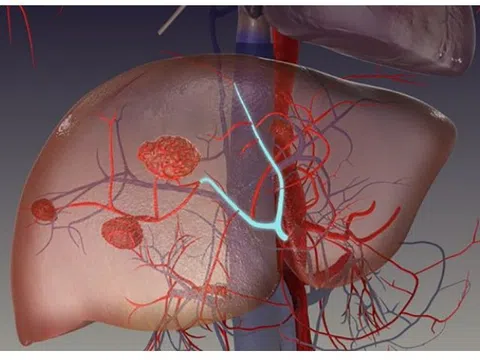

Đau tức hạ sườn, ăn kém, sút cân… là dấu hiệu bệnh gì?

00:01 08/01/2026

U máu gan là dị dạng mạch máu bẩm sinh và là khối u lành tính hay gặp nhất ở gan. Nhiều người nhập...